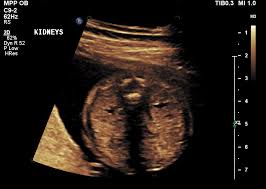

New Born baby with single kidney (Renal agenesis)

New Born baby with one kidney.

What will be the line of treatment for this rare birth defect (disorder)?

• download (84).jpeg

download (84).jpeg

3.7 KB · Views: 177